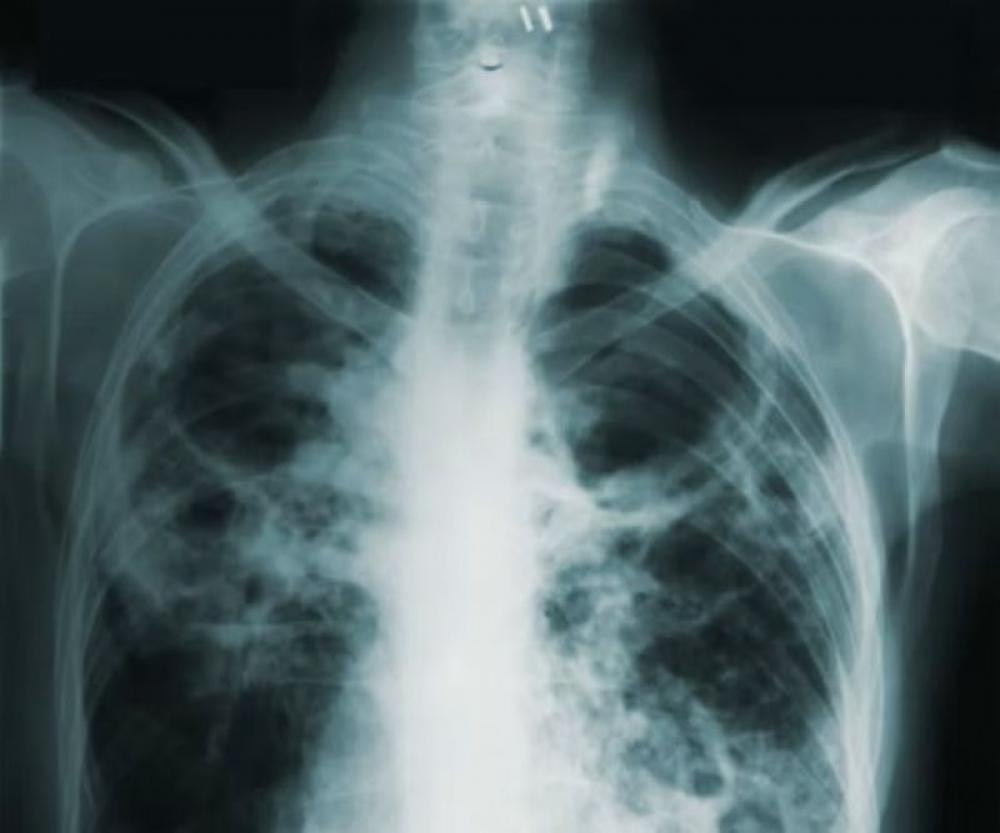

TB Pulmonary tuberculosis. Photo: Unsplash

Tuberculosis (TB) remains one of the world’s deadliest infectious killers, claiming over 1.2 million lives and affecting an estimated 10.7 million people last year, according to the WHO Global Tuberculosis Report 2025, released recently.